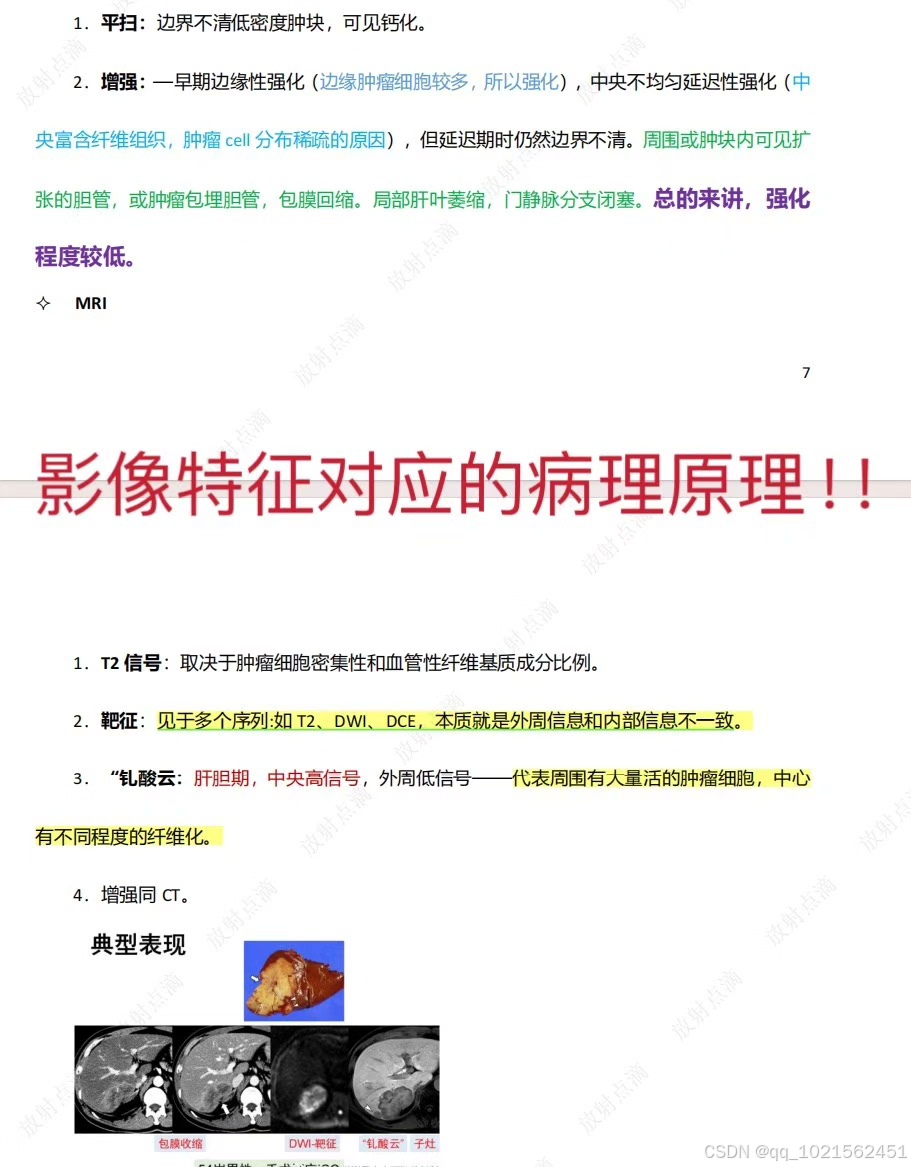

规培结业考试已通过,现分享自己花了大量时间和精力根据考点做的重点笔记,里面包含实际病例影像图片帮助记忆,横向和纵向鉴别诊断表格等,适合看不下去教材,没时间梳理和总结重点的朋友。

笔记来源:最初是为了研究生复试,收集了各个院校的笔试大题和面试专业题题干,然后根据教材的知识点,辅以各种其他书籍、专业公众号整理的答案,这里面不是单纯知识点的罗列,而是结合了实际考题进行了有逻辑的梳理,里面有很多鉴别诊断的表格,还有思维导图。最后背了自己整理的资料,考研面试成绩第一。后面在规培的过程中根据规培大纲和日常写报告的经验,又如法炮制,进一步完善了这份笔记,在规培结业考试的时候就直接省去了看教材这个过程,为我大大提升了效率,缩短了复习时间!!!!